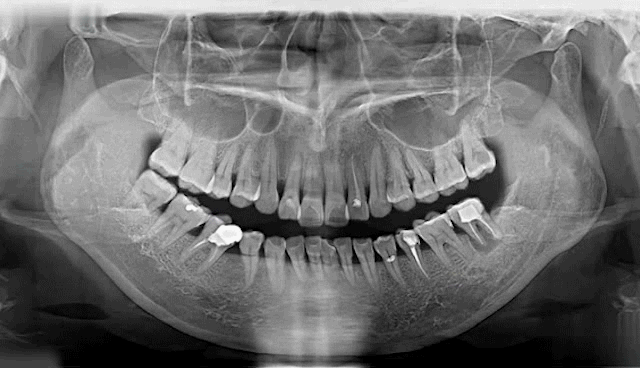

據(jù)醫(yī)學(xué)調(diào)查統(tǒng)計(jì)

我國35歲以上人群中

逾88%的人存在蛀牙等口腔問題

65歲以上的老年人群中

平均缺牙數(shù)量超過11顆

蛀牙率近98.4%,而調(diào)節(jié)率僅1.9%左右

▲Deepcare AI分析模擬未來10年口腔變化情況

牙齒脫落是由齲齒、牙周病等口腔問題導(dǎo)致的,不是單純的老化現(xiàn)象。牙齒健康至關(guān)重大,所謂“缺牙一顆,全口遭殃”,牙齒缺失一顆會(huì)引起鄰牙松動(dòng)、對牙伸長、引發(fā)牙周病,終導(dǎo)致余牙逐漸脫落等一系列問題,還會(huì)因咬合紊亂致使面容蒼老、咀嚼功能變差引發(fā)腸胃疾病,嚴(yán)重影響身體健康。